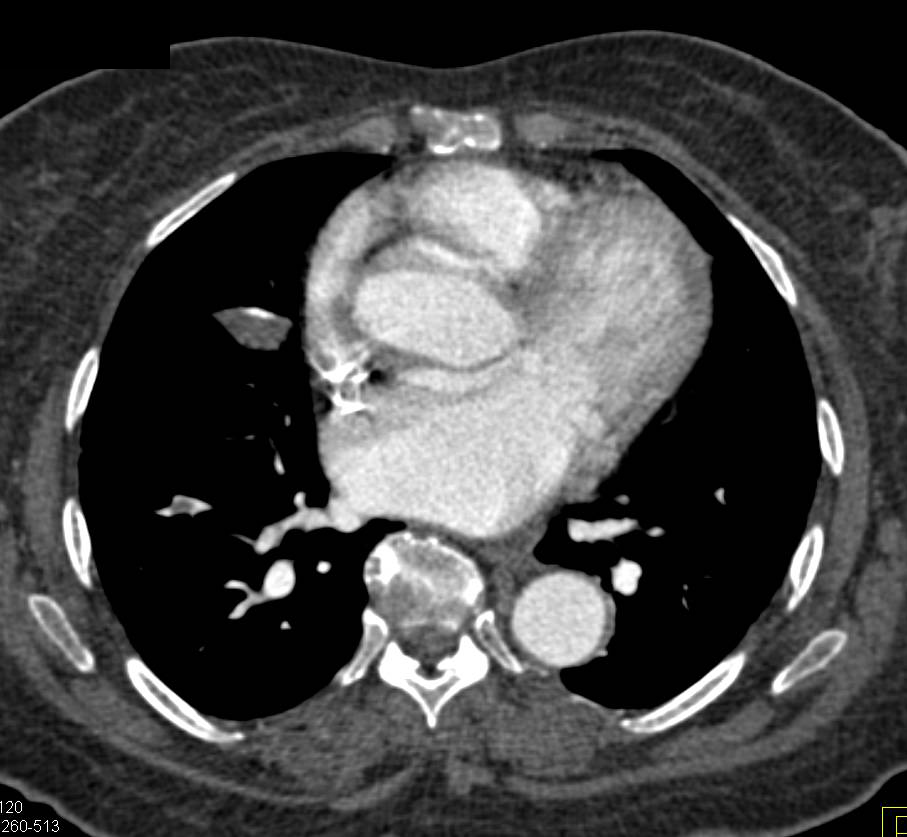

Incidental Pulmonary Embolism (PE) in Patient seen in Multiple Perspectives